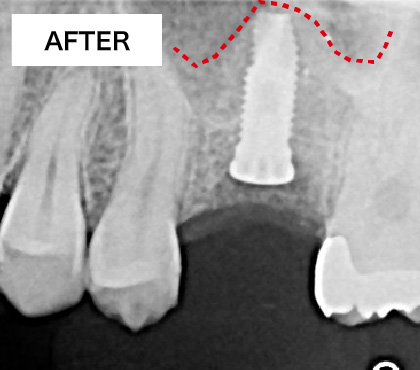

上顎洞が上に押し上げられ、インプラントを埋入するスペースができました。骨の材料も充填されているのでインプラントは安定します。

ソケットリフト方法

歯肉を切開します。

骨をドリルで切削します。

上顎洞の壁を押し上げます。

骨の材料を充填します。

インプラントを埋入します。

BEFORE・AFTER